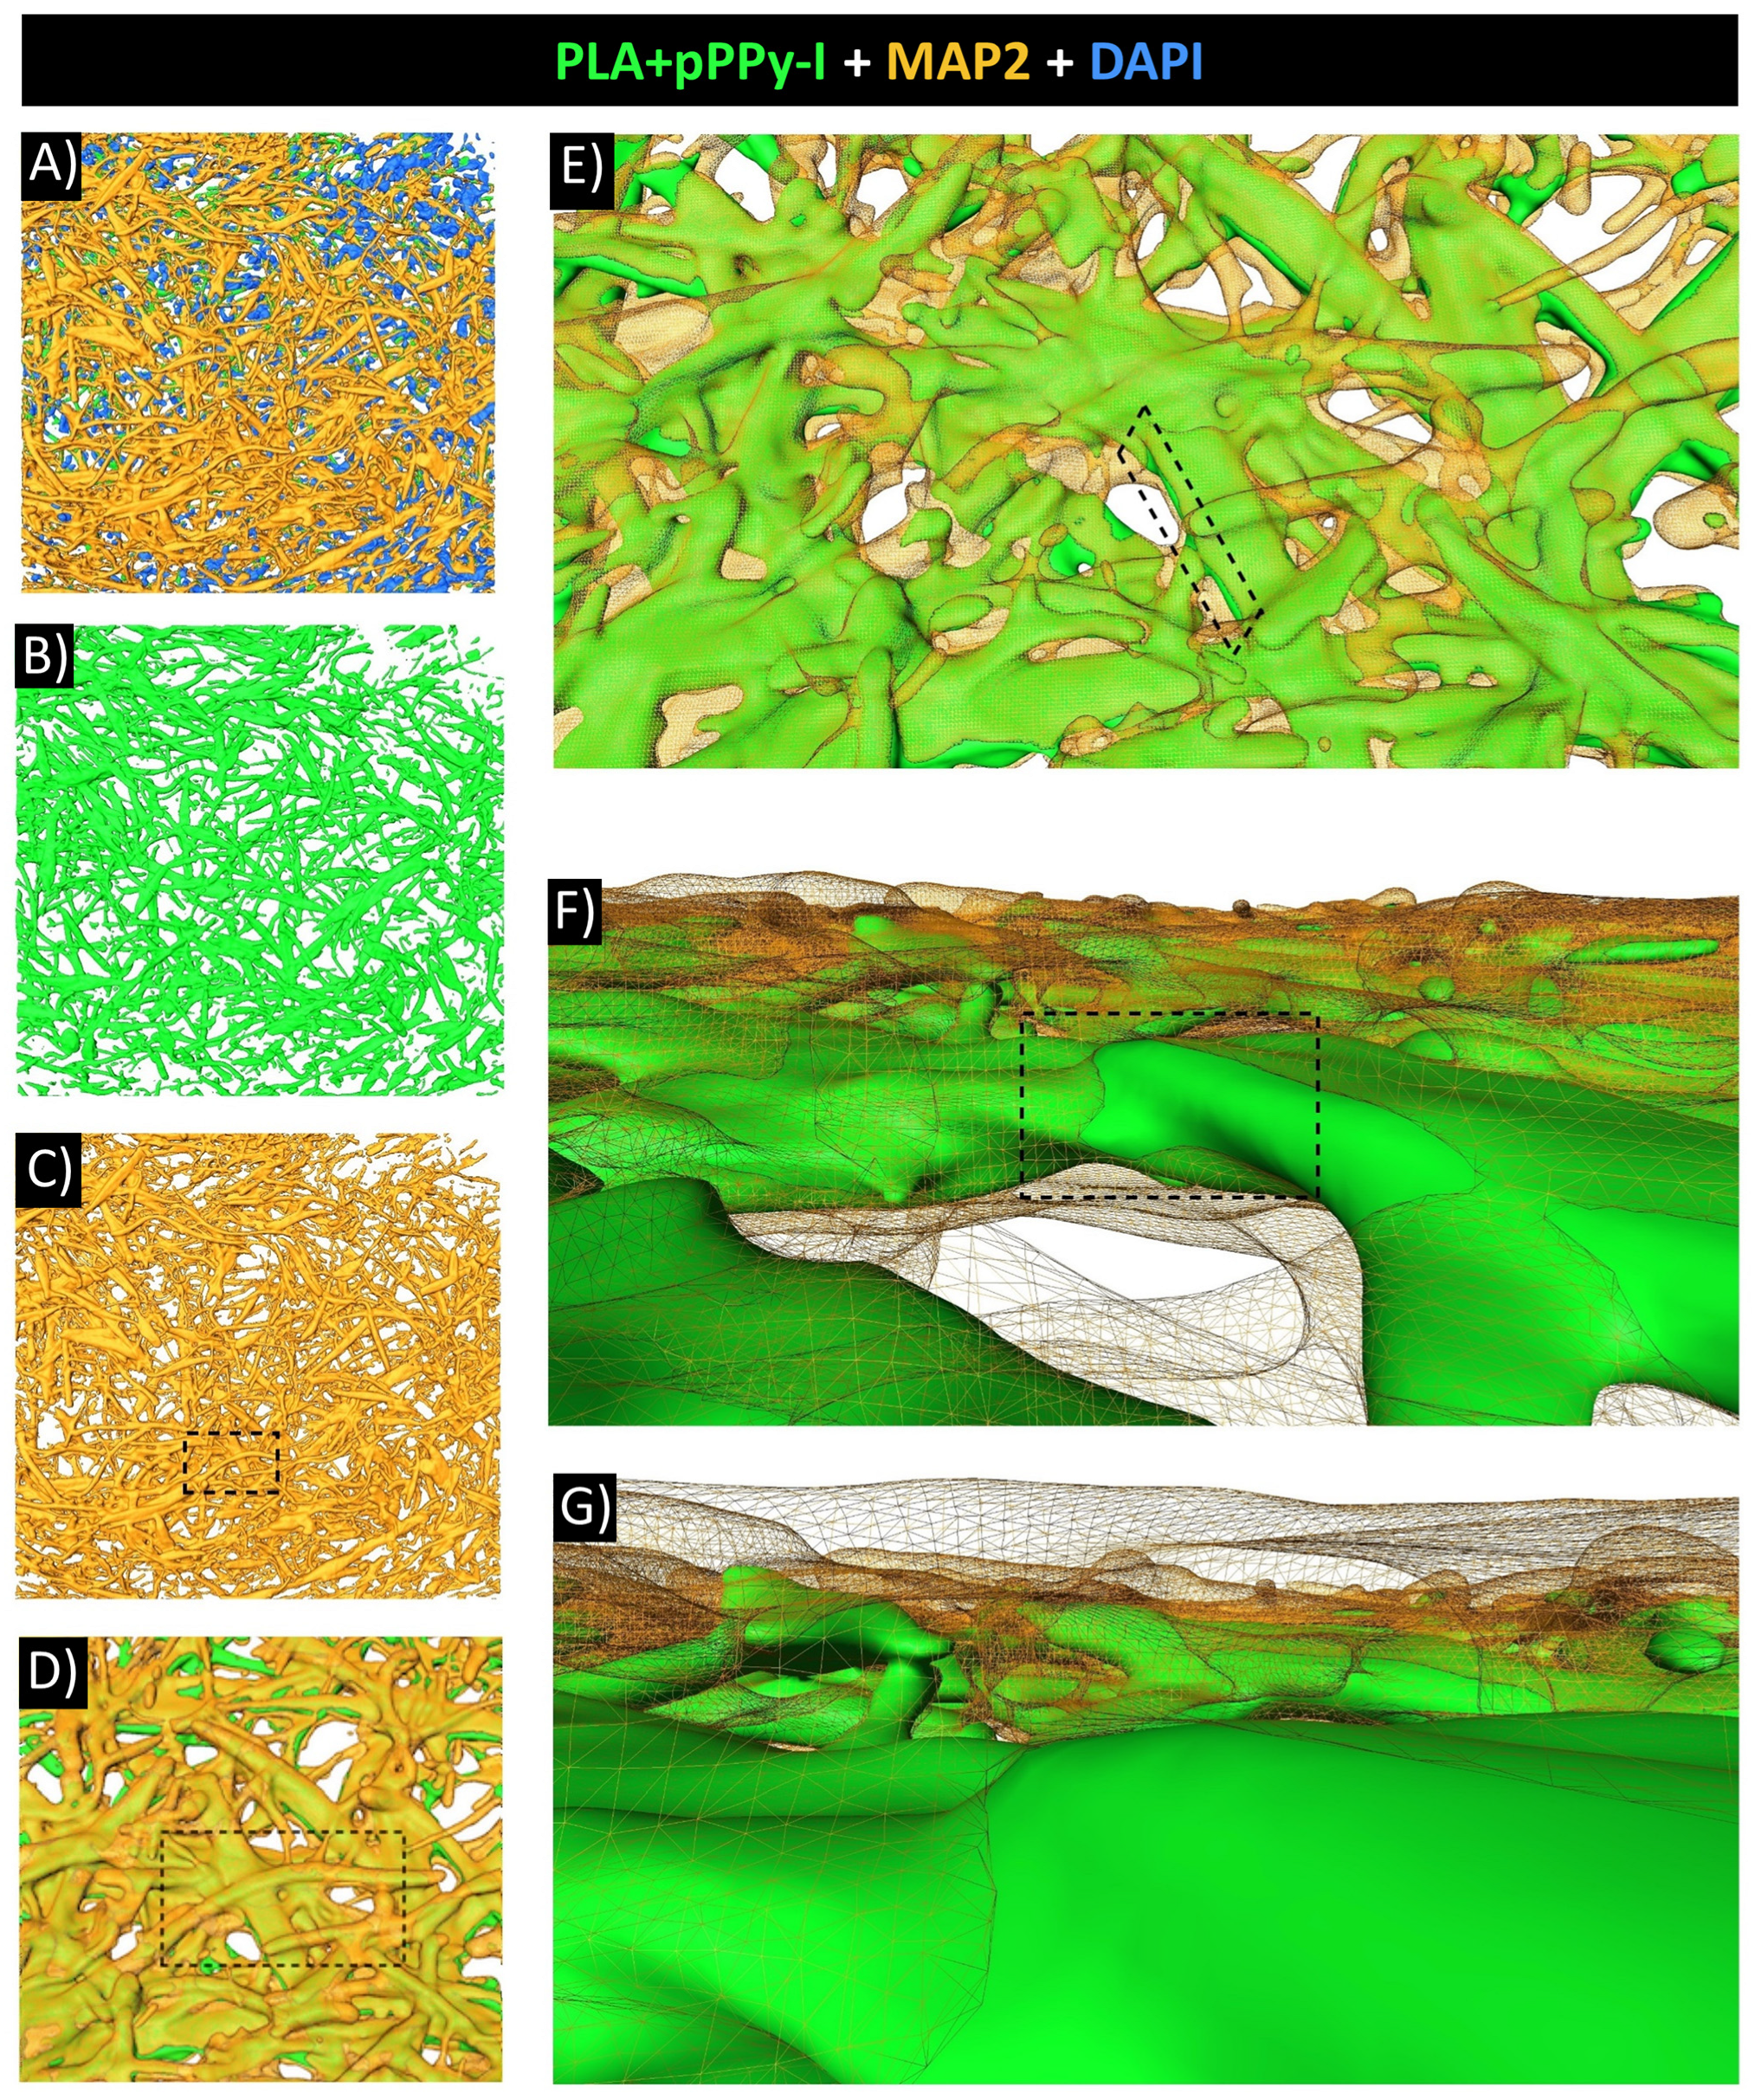

3.8. Evidence of Neuronal Marker MAP2 over the Fibers Demonstrated Fibrillar Scaffolds Are Potential Substrates for Nerve Repair